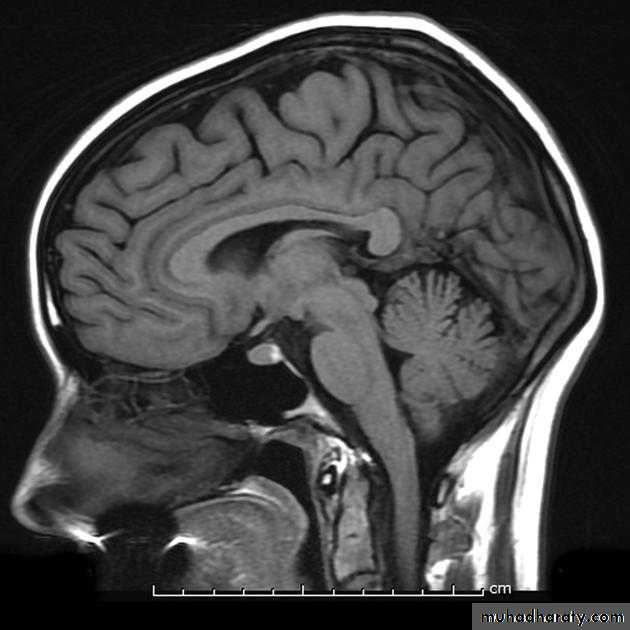

Ventricles

Lateral

Third

Fourth

Flow of CSF:

• The CSF passes from the lateral ventricles (I and II) through the foramen of Monro into the third ventricle (III) then through the aqueduct of Sylvius into the fourth ventricle (IV) and out into the subarachnoid space through the foramina Lushka & Magendie .Absorption of CSF